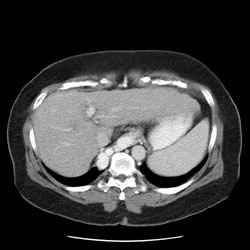

RADIOLOGY: ABDOMEN: Case# 34017: VERY LARGE VARACES. 57 year old female with hepatitis-C. 1. Cirrhotic liver configuration without evidence of focal leisons. 2. Splenomegaly. 3. Enormous esophageal varices.